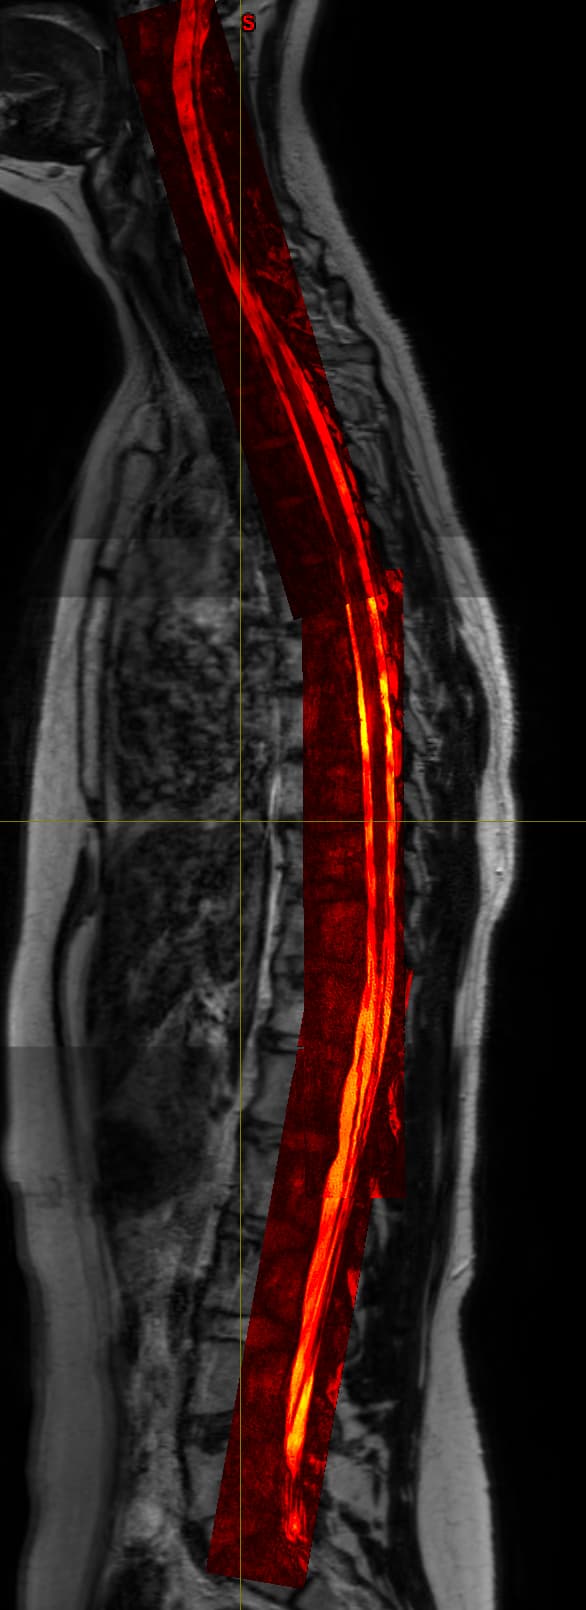

I have acquired some simple T2 images that are easily concatenated as the xyz-axis for all images is the same so I have cervical, thoracic and lumbosacral parts that I can join into 1 spinal cord T2 image. Now I also have some high detail images that only contain the spinal canal and little surrounding tissue with very high contrast within spinal canal but these are also in 3 parts but oriented along the spinal cord. So these 3 images do not have the same orientation which causes them to not be “stitchable”. I already tried getting them to a similar template/orientation but nothing seems to really work. The sct_image either returns only part of the images or just removes parts. While when you visualize them after registering them to the T2 they lie perfectly over eachother, so it is just an orientation problem.

Do you have any ideas on how to get them concatenated? Maybe straighten them separately, then register them to the straightened total T2 and then stitch?